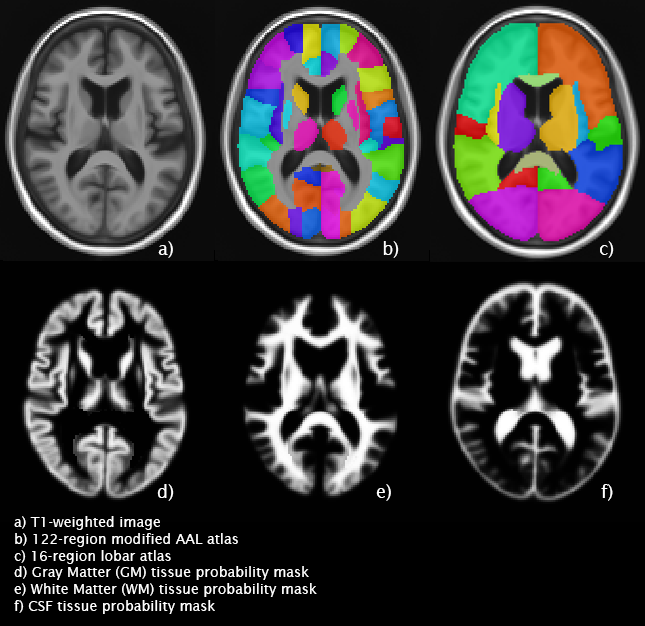

Mayo Clinic Adult Lifespan Template and Atlases

Mayo Clinic Adult Lifespan Template and Atlases Images

1 Images available.

Description: